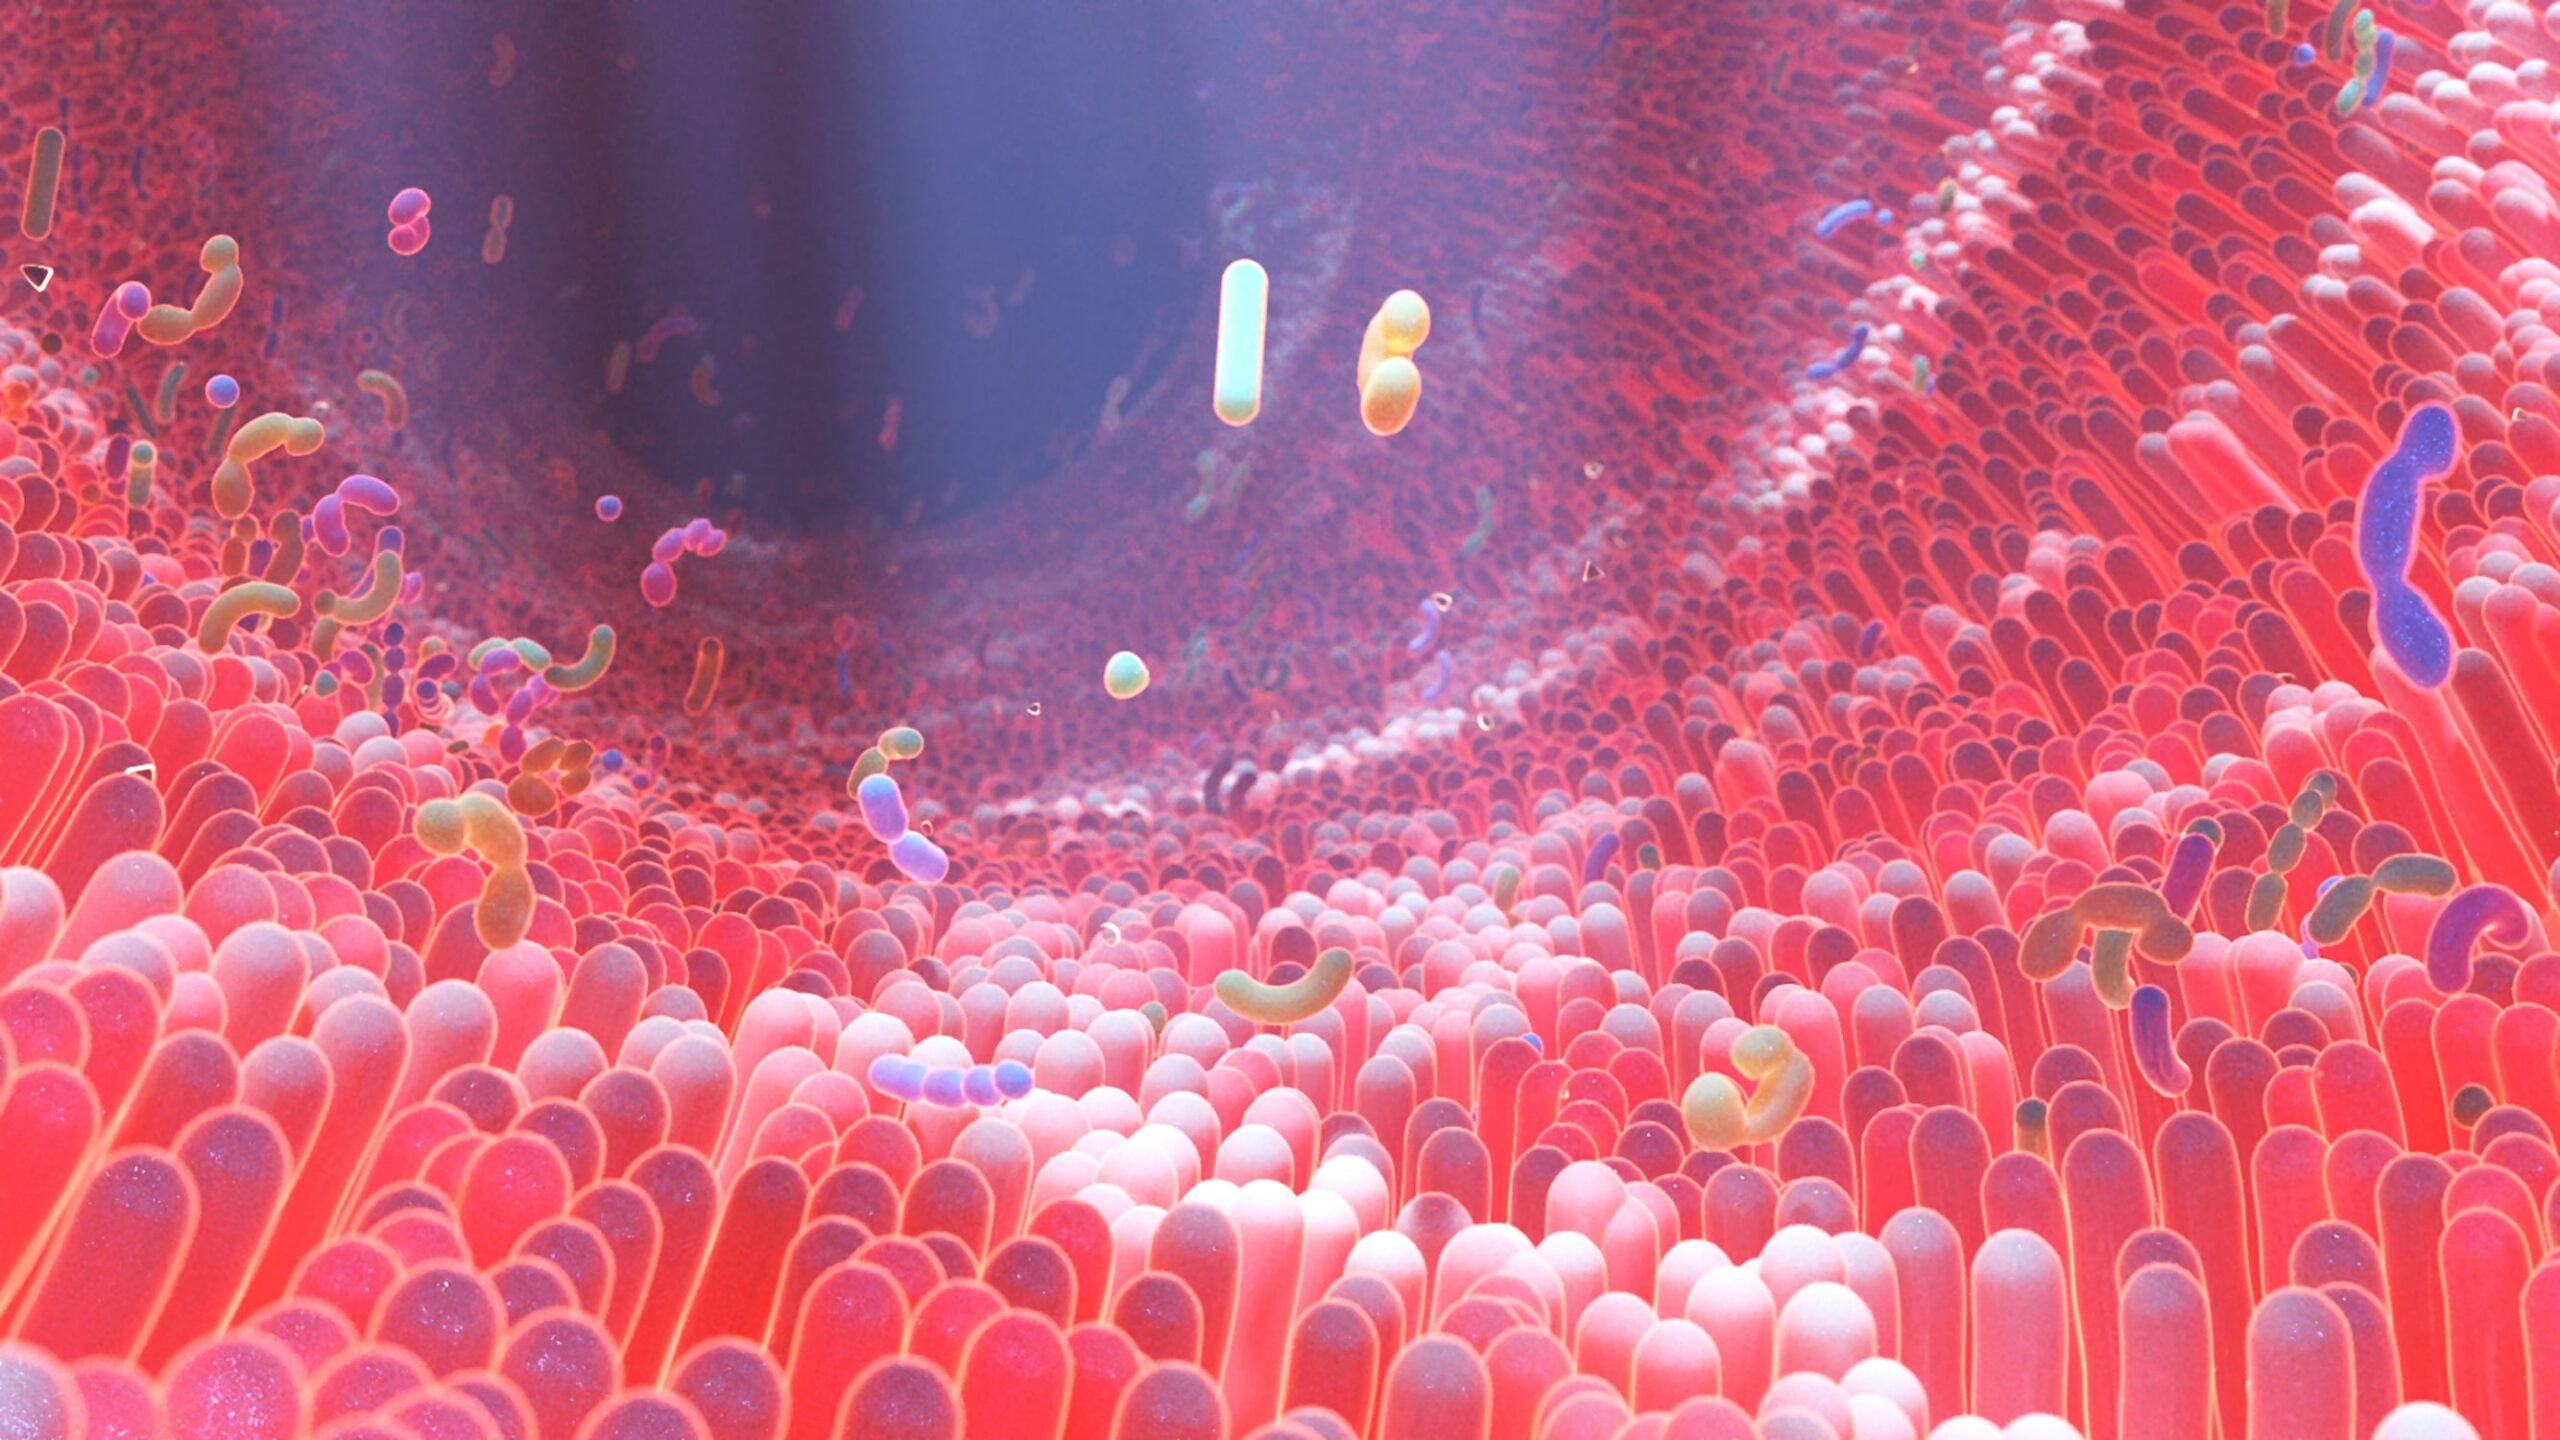

JK5G postbiotics may improve gut microbiota, QOL, and appetite in patients with advanced NSCLC on PD-1 inhibitor therapy.